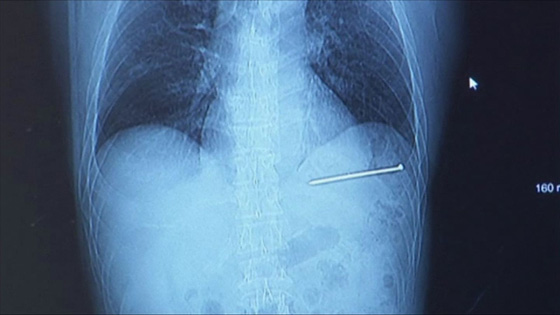

وقال بيرجسون في مقابلة صحفية"اعتقدت أنها لم تخرج مني. شعرت بخير، لم أكن قلقا بشأن الإصابة، لم أشعر بأي ضغط أو دماء". وأضاف بيرجسون (52 عاما) إنه كان يرى فقط حوالي 1 بوصة من مسمار 3½ بوصة يخرج من صدره. وقال: "كان بإمكاني رؤية المسمار يتحرك مع ضربات القلب، وكان ذلك يحدث مع كل ضربة من ضربات القلب".

وقال بيرجيسون إنه بدأ يشعر بالمزيد من الألم واستدعى حارس أمن للحصول على المساعدة. وبعد أخذ الأشعة السينية، تم نقل بيرجيسون بواسطة سيارة إسعاف إلى مركز أورورا بايكار الطبي في جرين باي. وقال بيرجسون: "عرضت أن أقود بنفسي، لكنهم لم يسمحوا لي".

وأكد الدكتور ألكسندر رويتشتاين "ضرب مسمار قلب بيرجسون"، قائلاً إنه كان على بعد 1/16 من بوصة واحدة من الشريان الرئيسي. وقال إنه من الصعب تقييم مدى عمق اختراق المسمار، ولكن المسمار ترك كدمات وحفرة. وأثنى على بيرجيسون لعدم سحب المسمار والسماح للأطباء بمعالجته.

المسمار كان على بعد 1/16 من بوصة واحدة من الشريان الرئيسي